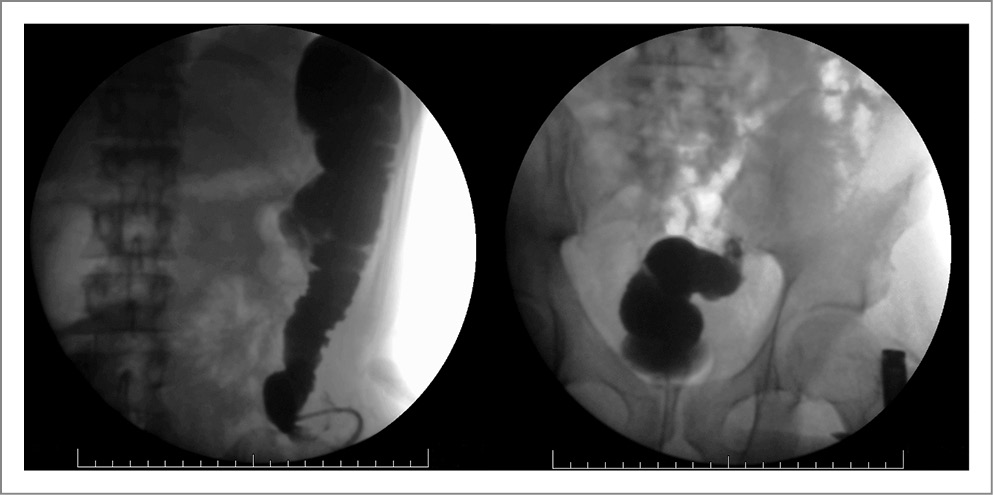

В план операции входило устранение колостомы и наложение десцендо-сигмоанастомоза. Факторы риска развития операционных осложнений: мужской пол, курение, саркопения, нутритивный дефицит, длительность оперативного вмешательства, выраженный спаечный процесс. Для минимизации риска несостоятельности швов анастомоза произведена оценка выраженности саркопении. Оценка состава тела производилась путем сегментации изображений в сагиттальном срезе на уровне LIII-позвонка, полученном по данным КТ.

Рис. 3. Послойное изображение (кожа, кишка).

Перед планированием операции произвели оценку морфологического и физиологического состояния кишечника, а также оценили особенности и распространенность спаечного процесса. Для этого выполнили КТ с внутривенным и пероральным контрастированием с последующей сегментацией изображений и 3D-реконструкцией с использованием набора программных инструментов SliceOmatic, OsiriX, InVesalius. Пероральное контрастирование с отсроченной КТ подтвердило отсутствие обструкций и нарушений пассажа контрастного препарата по кишечнику. Таким образом, доказана нецелесообразность выполнения тотального адгезиолизиса, что уменьшало травматичность и длительность планируемой операции.

Рис. 4. Участки кишки, максимально припаянные к передней брюшной стенке.

Методику выполнения хирургического доступа и его локализацию, учитывая распространенность спаечного процесса, рассчитали с помощью 3D-моделирования сегментированного изображения (рис. 2–4). В автоматическом режиме выделены пиксели плотностью от -226 HU до 3071 HU, что соответствовало рентгенплотности кожи и подкожной клетчатки. Проведенное исследование позволило выделить зоны адгезии толстой и тонкой кишки к брюшной стенке, представляющие повышенную опасность для выполнения доступа.